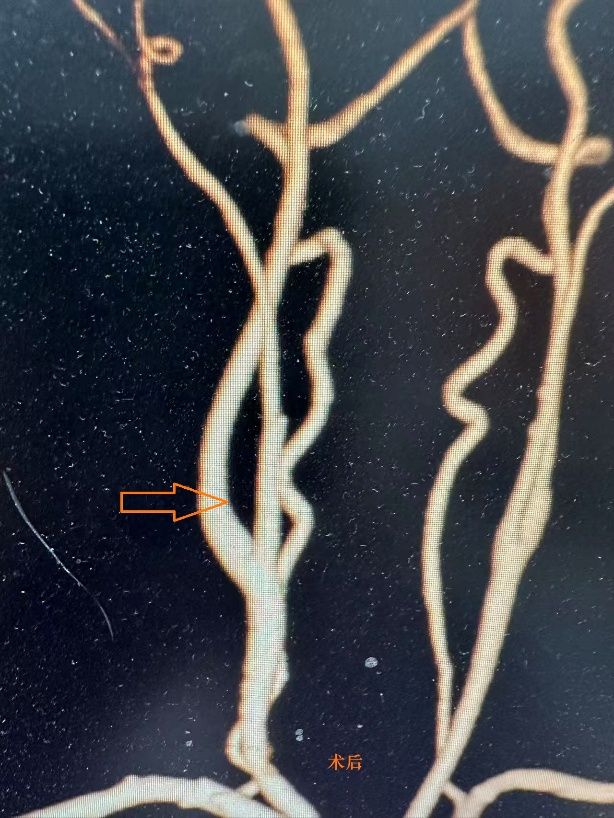

手术在任晓勇主任现场指导,许映龙副主任医师主刀,郭立主治医师、张楚彤医师、张勇麻醉师及手术室黄新坤和王泽宇等护理团队密切配合下顺利实施。术中探查发现,肿瘤位于颈总动脉分叉处,体积较大,肿瘤与颈外动脉之间的粘连程度明显重于术前影像学评估,肿瘤包绕血管并形成致密纤维性粘连,同时肿瘤周围存在丰富而复杂的供血血管网。在分离过程中,部分滋养血管破裂,出现较为迅猛的出血情况,手术团队迅速启动预设方案,采取精准止血及血流控制措施,同时为患者输注红细胞悬液2U以维持循环稳定。面对复杂的解剖关系和术中出血风险,团队协作,精细操作,最终成功将肿瘤完整切除,颈内、颈外动脉血流恢复良好,重要神经结构完好无损,手术顺利完成。

术后患者生命体征平稳,经密切观察未出现声音嘶哑、吞咽困难或肢体感觉异常等颅神经损伤表现,恢复良好,于术后4天出院。